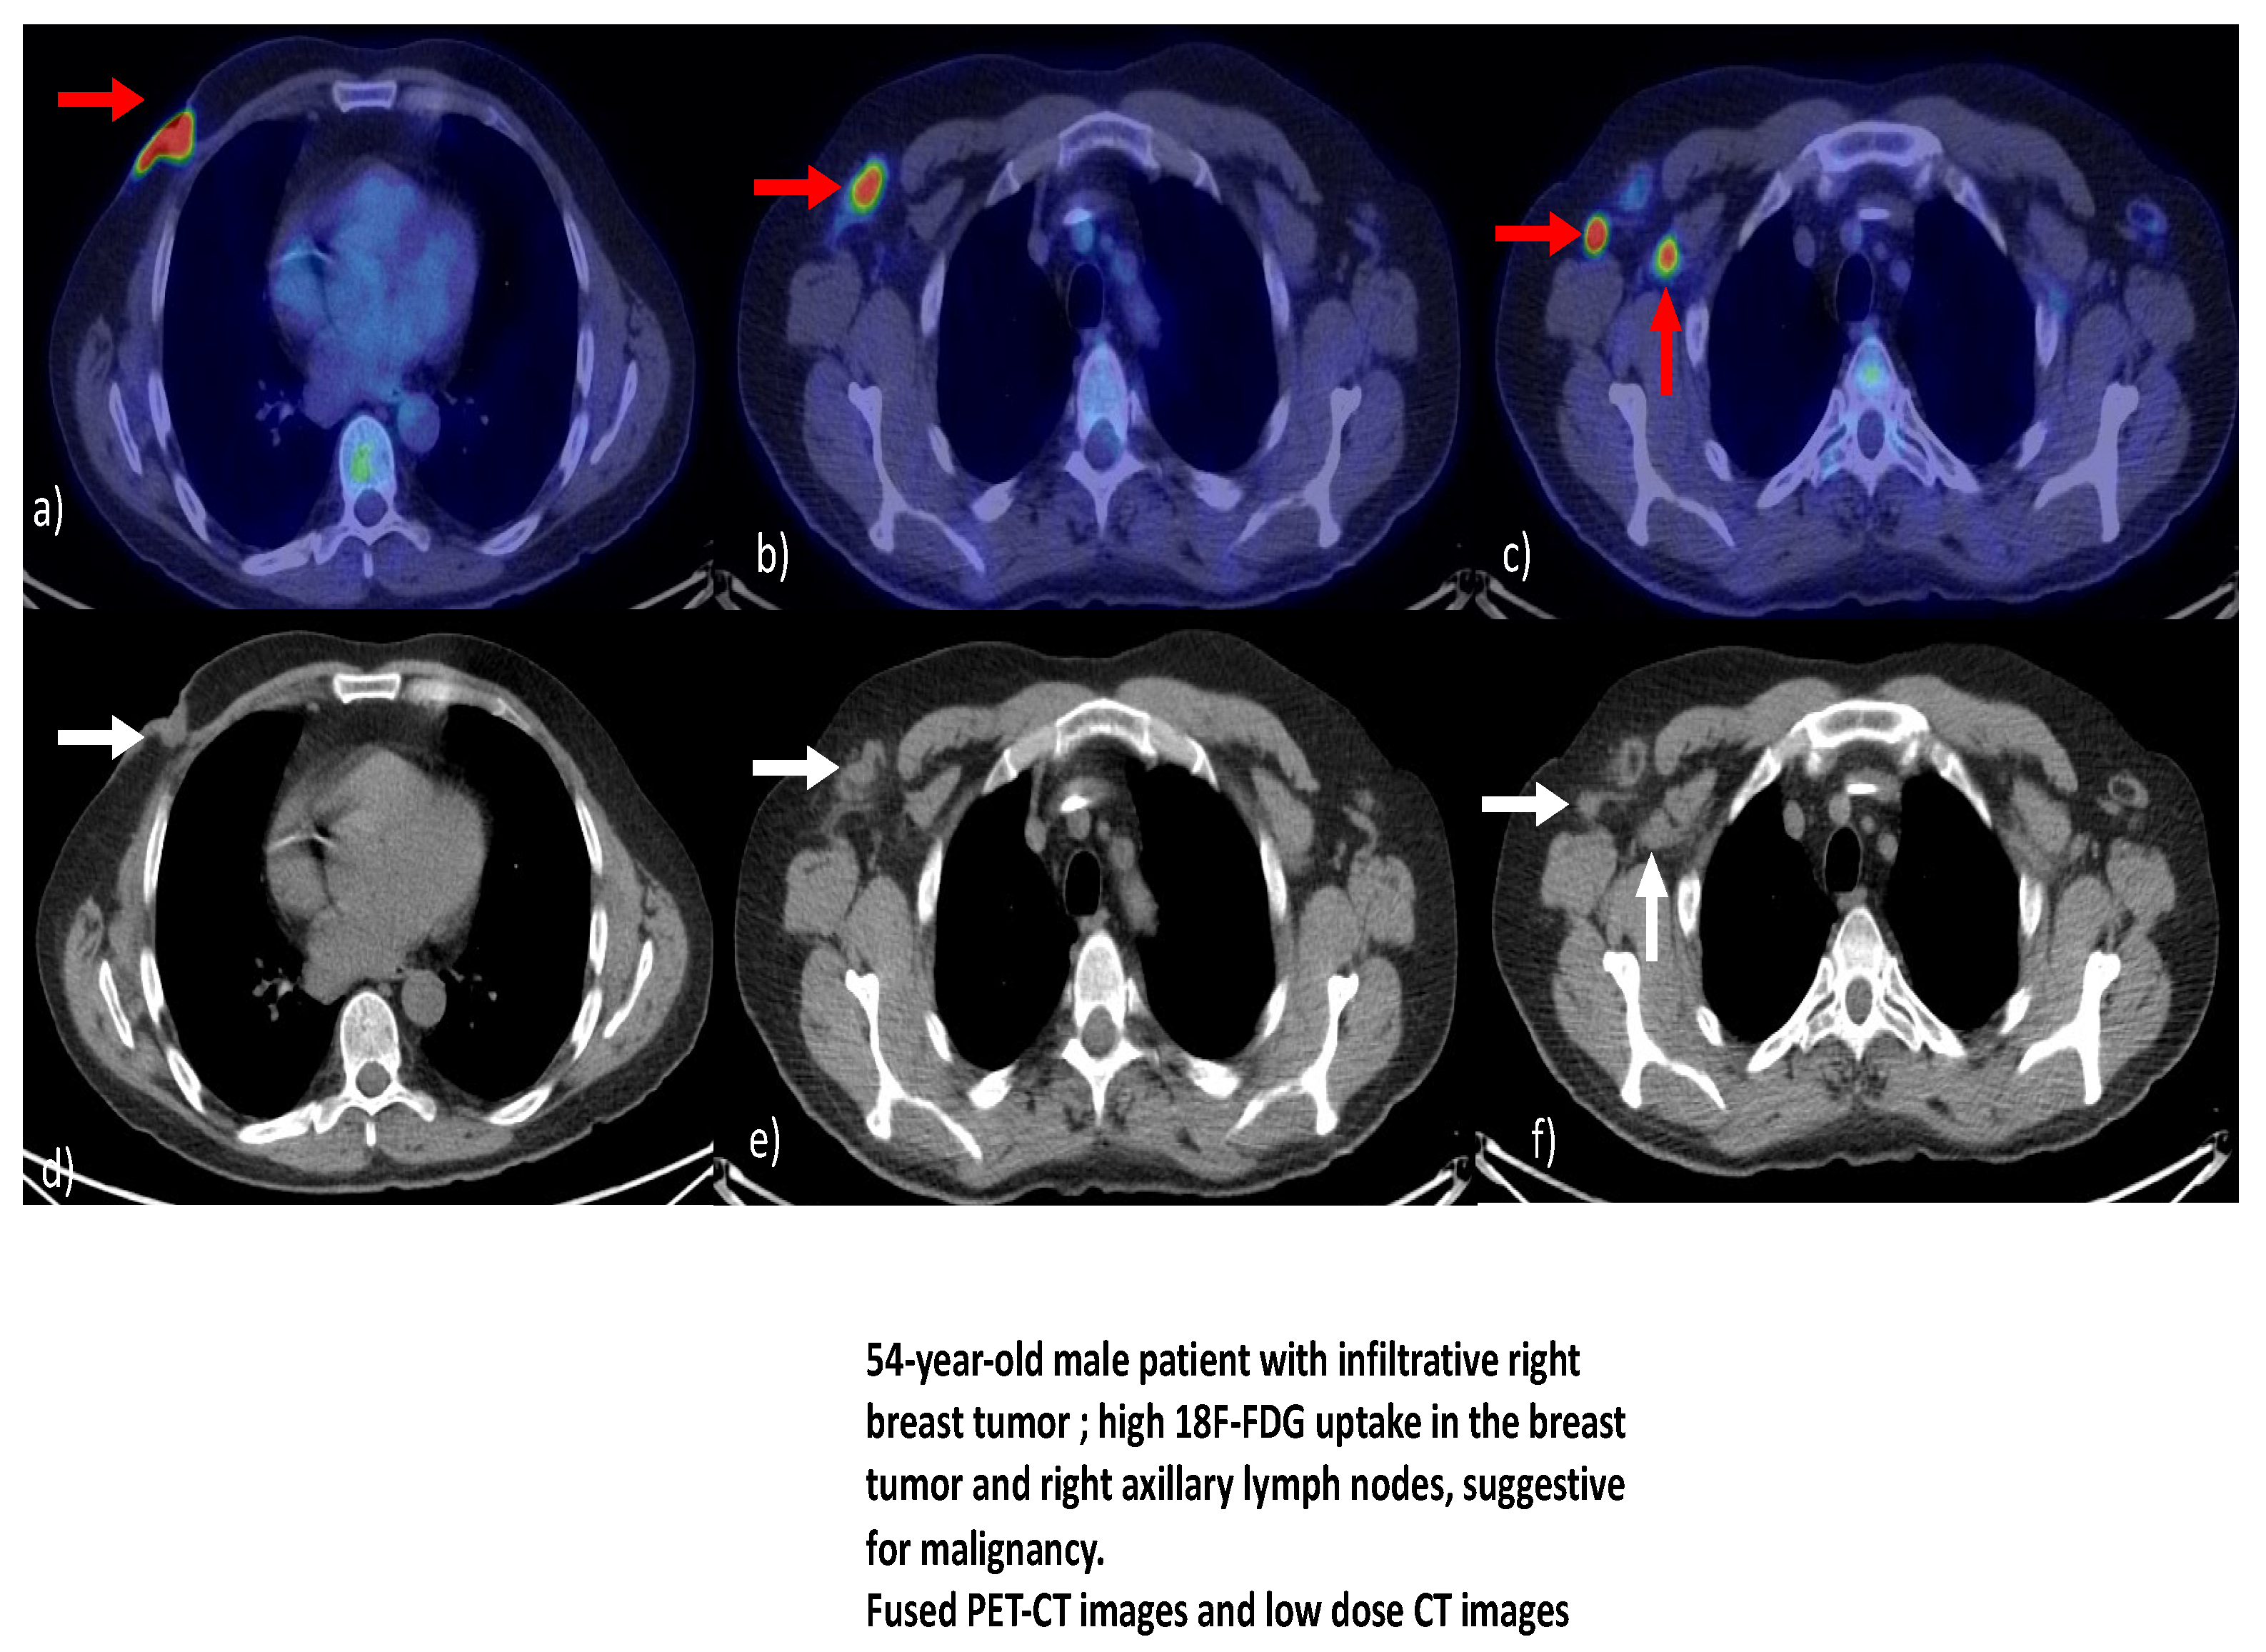

In a systematic review by Dondi [41], which aimed to analyze the diagnostic performance and utility of 18F-FDG PET/CT in the evaluation of MBC, it was found that, despite the limitations of the review, 18F-FDG PET/CT appears to be an effective method for assessing MBC. The conclusion continued with the idea that further research is required to clarify the role of hybrid imaging with 18F-FDG in the evaluation of MBC, particularly in comparison to breast cancer in females. Figure 1a–f illustrates various aspects of PET-CT in a patient diagnosed with mail breast cancer.

Figure 1.

(a–f) Subsets illustrating PET-CT/ low dose CT aspects of male breast tumors. Courtesy of Dr. Mirela Gherghe, affiliated to the Nuclear Medicine Department of the Bucharest Oncology Institute and “Carol Davila” University of Medicine and Pharmacy, Bucharest, Romania.